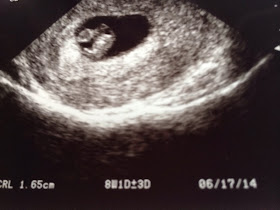

We were referred back to the MFM (maternal fetal medicine Dr.) for precautionary reasons since Scarlett had a 2 vessel cord. We went Wednesday at 12w1d for the nuchal Translucency (NT) screening and genetic blood work. The NT measurement was awesome and the blood work was perfect! It was too early to tell how many vessels the cord was but we go back for the anatomy scan at 18 weeks.

| 12w1d measuring 12w5d due to a 13w1d head! |

The baby was very active - kicking and wiggling all over. I saw it open and close it's mouth. It kept both legs completely stretched out the entire time.